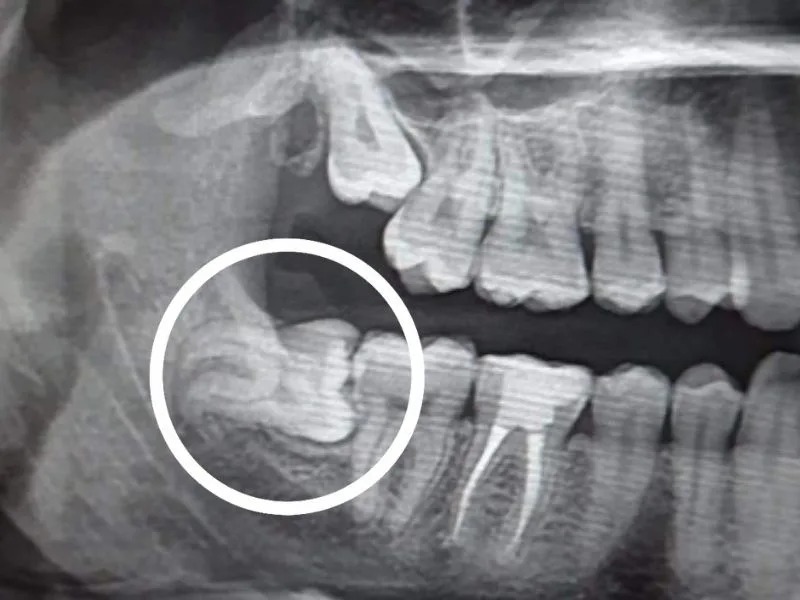

Oral Surgical Procedures